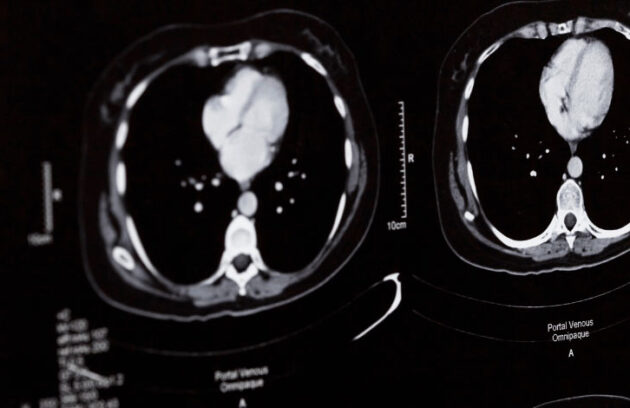

Tal projeto pode propor métodos inovadores na detecção, tratamento e prevenção de doenças, incluindo o câncer

Entenda os riscos e sintomas do câncer de intestino, fator que causou aumento no número de internações nos últimos anos